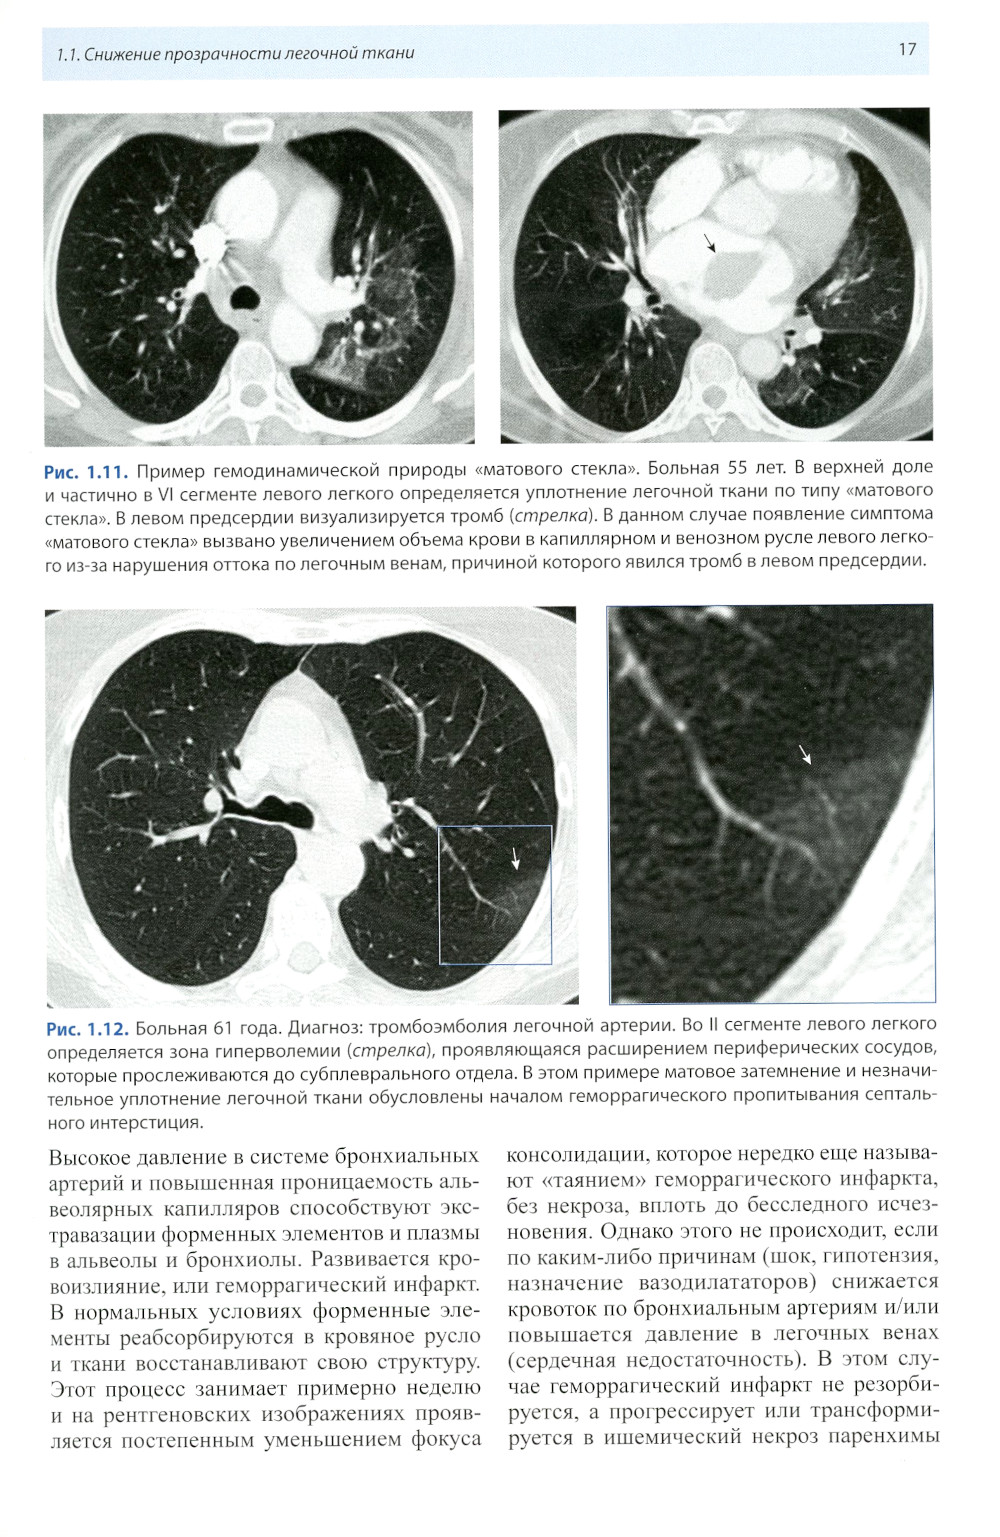

Книга составлена из двух разделов. В первом (глава 1) описаны основные симптомы патологии легких, выявляемые при КТ. Каждый из них представлен с позиции отображающих его морфологических изменений. В краткой форме описаны заболевания, проявляющиеся конкретным симптомом. Второй раздел книги состоит из трех глав, в которых отражены современные взгляды на наиболее часто встречающуюся патологию легких (пневмония, туберкулез, рак) и показаны возможности КТ в выявлении этих заболеваний. Издание предназначено для врачей лучевой диагностики, терапевтов, интернов и студентов старших курсов, интересующихся проблемами рентгенологии.| Издательство | МЕДпресс-информ |